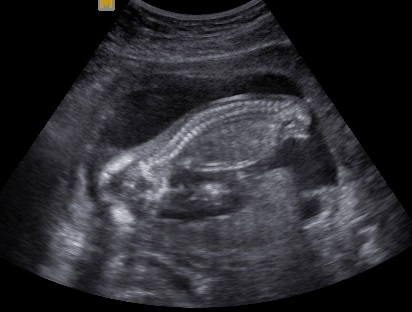

Columna vertebral

La columna vertebral, el eje neurológico que articula las funciones motrices y autonómicas del cuerpo comandadas por el cerebro y los sistemas vegetativos, es una estructura lineal mas sencilla de evaluar pero no menos importante desde el punto de vista diagnóstico por ser el asiento de las malformaciones más comunes del sistema, la espina bífida.